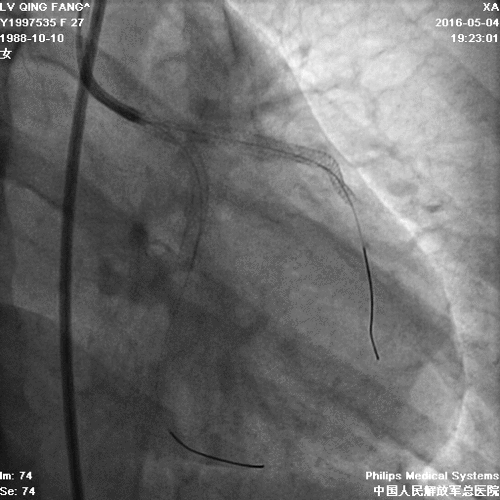

造影

PCI